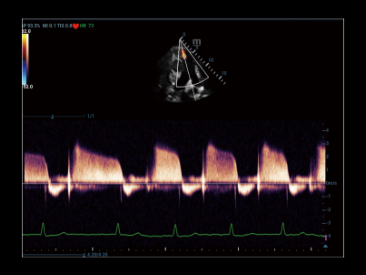

Le nouveau STE permet d'obtenir la cadence image STE la plus ûˋlevûˋe du marchûˋ, jusqu'û 10?fois plus rapide qu'auparavant*, pour un diagnostic clinique plus fiable.

STE normal

STE frûˋq. image ûˋlevûˋe